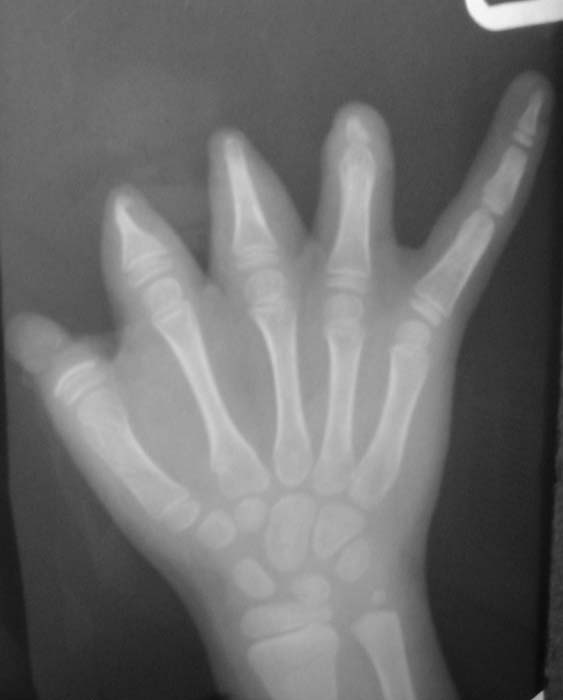

Уважаемые коллеги! Девочка, 6 лет. Врожденная аномалия развития кистей и стоп. Вопрос: лечение? В приложении - рентгенограммы и клинические фотографии Заранее благодарен! С уважением, А.В.Владзимирский